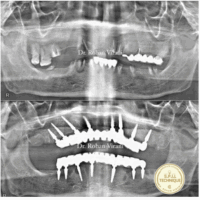

Case Study 1 (Female)

pre op opg spil technique

post op opg spil techinque